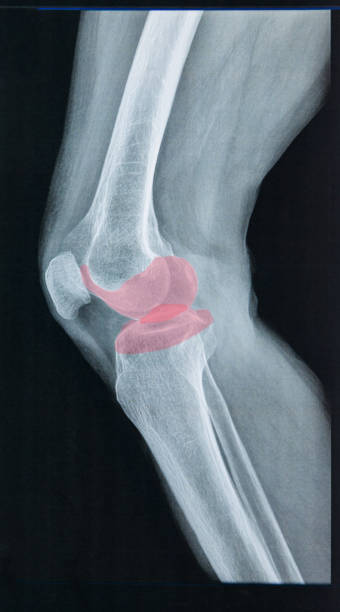

연골손상에 의한 무릎 통증

연골은 뼈와 뼈 사이의 마찰을 줄이고 충격을 흡수하는 기능을 합니다. 무릎의 연골손상은 무릎 통증의 일반적인 원인 중 하나입니다. 연골손상은 다양한 원인으로 발생할 수 있으며, 가장 흔한 원인은 무릎 관절 내의 충격이나 비대칭적인 압력에 의해 발생하는 외상입니다. 연골손상은 통증, 부종, 불안정성, 감각 손실 등의 증상을 일으킬 수 있습니다. 치료는 무릎 관절을 안정시키는 운동, 연골 재생을 촉진하는 약물 치료, 수술 등이 있습니다.

전방십자인대 파열에 의한 무릎 통증

전방십자인대는 무릎을 지탱하는 중요한 인대 중 하나입니다. 이 인대가 파열되면 무릎이 불안정해지며, 걷거나 달리는 등의 운동 시 무릎이 흔들리거나 무력감이 느껴집니다. 무릎 통증, 부종, 불안정감 등의 증상이 나타나며, 복합적인 치료가 필요합니다. 치료에는 수술적 치료, 전문가의 지도하에 진행되는 재활 운동 등이 포함됩니다.